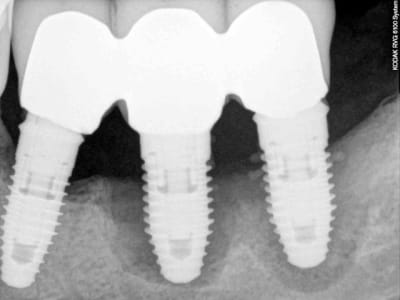

7 les radios post-op

ce qui parait évident de prime abord, c'est le manque d'adaptation des couronnes.